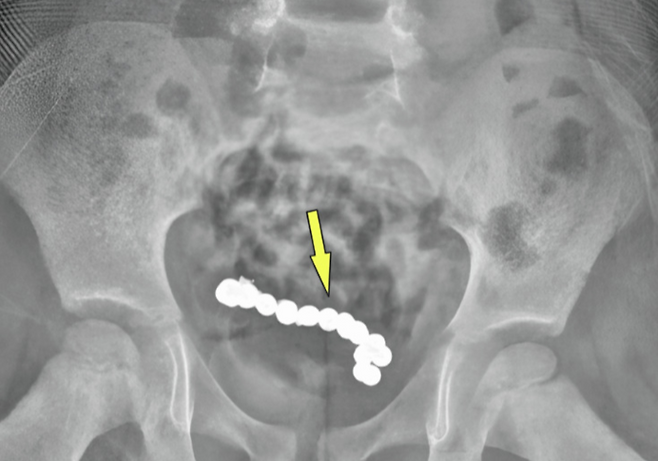

그러나 A군의 상태는 호전되지 않았다, 의료진은 A군의 복부 CT를 촬영을 결정했다. 그 결과 A군의 하복부에 동그란 모양의 이물질들이 사슬처럼 연결돼 있는 것을 확인할 수 있었다. 의료진은 복강경 수술을 진행했다.

이물질의 정체는 22개의 자석이었다. A군은 자석의 인력으로 인해 괴사된 장의 약 15㎝를 절제했다. A군은 4일 만에 안정된 상태로 퇴원했다. 3개월 뒤 진행된 추적 관찰에서도 특별한 이상 소견이 발견되지 않았다.